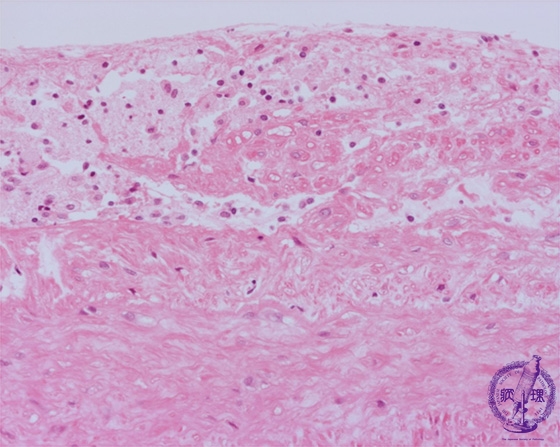

- ★(9)Atheroslerosis (aortic atherosclerosis) li>

Microscopic image (HE, high power view): Sub-endothelial lipid accumulation within foamy (lipid laden) macrophages (blue circles). The elastic lamellae of the tunica media is partially effaced (red line).